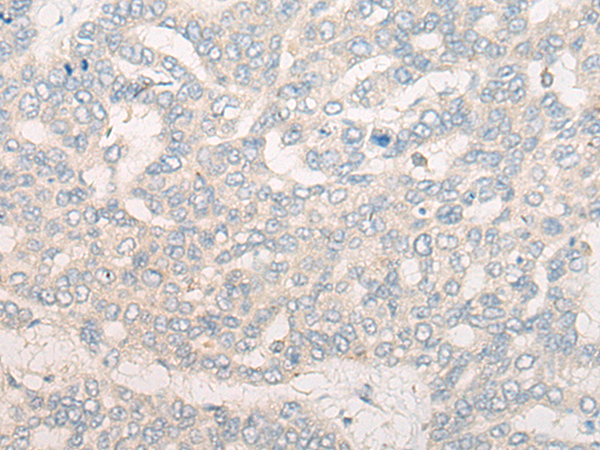

IHC positive control: |

Human liver cancer and Human gastric cancer |